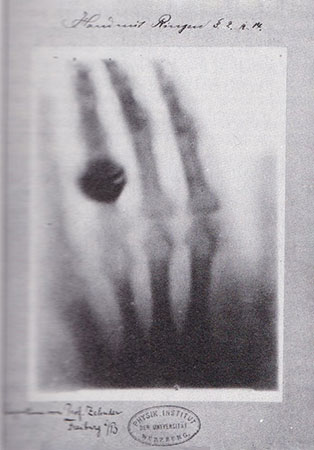

The first observation of the potential of hyperthermia against cancer was made even before the discovery of X-rays in 1866 when a German surgeon Carl D. W. reported a case of tumor regression in a patient with sarcoma of the face after a high fever caused by erysipelas infections. A century later, a renewed interest in hyperthermia emerged to enhance the effects of radiotherapy. Animal experiments were encouraging. Equipment was designed to be used with external irradiation and interstitial brachytherapy. The challenge was to reach a homogeneous temperature of about 43 degrees (Celsius) and to control it in the irradiated volume. Such a goal was difficult to achieve since biological homeostatic processes were immediately reducing temperature by increasing blood flow. Clinical trials combining hyperthermia with radiotherapy showed that hyperthermia could sensitize tumor cells to radiation. A few randomized trials resulted in rather moderately significant outcomes. A randomized multicenter trial investigating the addition of a weekly hyperthermia treatment to radiotherapy of patients with locally advanced breast cancer was recently reported by Jens Overgaard [34]. This EHSO (European Hyperthermia Society for Oncology) trial held from 1987 to 1993, concluded to significantly enhanced 5-year tumor control and yielded more patients surviving free from cancer in the hyperthermia group. Outside research trials, some remarkable isolated results were obtained in local recurrences that were considered incurable by conventional means.